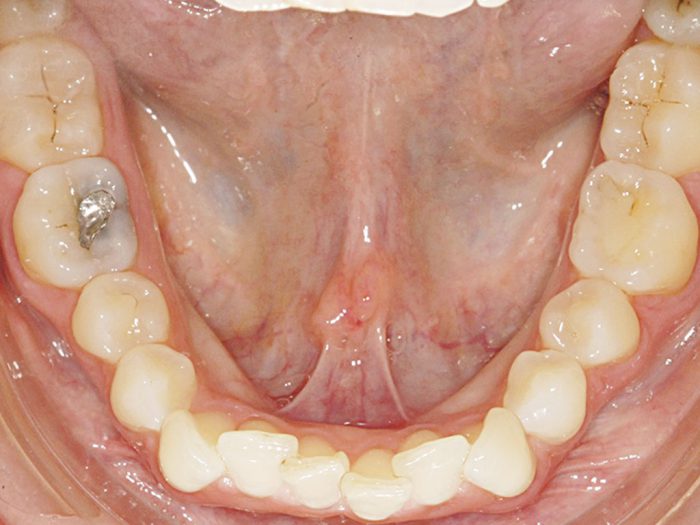

Lower Model of Patient with Lingual Tori » Lee Ann Brady, DMD's Dental Blog Dental Term Lingual An angle formed by the junction of two planes; Used to designate the junction of two surfaces of a tooth, or of two walls of a tooth. The teeth surfaces include distal, mesial, buccal, lingual, labial, occlusal, and incisal. Fully labeled illustrations of the teeth with dental terminology (orientation, surfaces, cusps, roots numbering systems) and detailed images. From dental procedures. Dental Term Lingual.